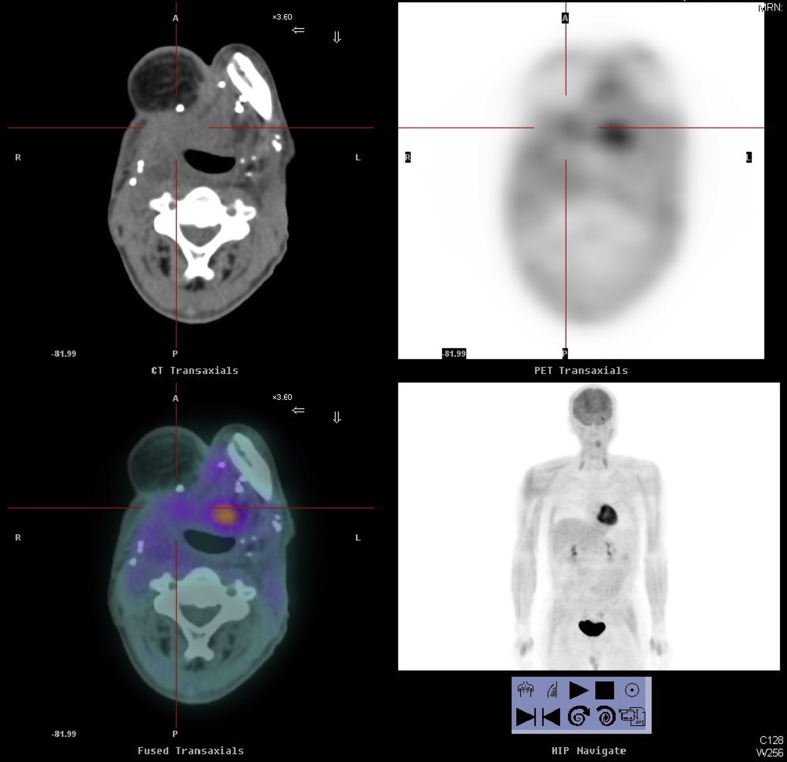

Two patients who did not undergo the imaging study post-SBRT were not evaluable in terms of the response. Among the 72 patients who were evaluable for the response after SBRT, the response rates meeting the RECIST criteria were CR: 25.0%, PR: 41.7%, SD: 11.7%, and PD: 21.7%. Sixty (83.3%) patients received a PET-CT scan approximately 2 months after SBRT. Of the 60 cases evaluable for the metabolic treatment response, the response rates according to the EORTC recommendations were CMR: 21.7%, PMR: 51.7%, SMD: 13.3%, and PMD: 13.3%. Fig. 2 depicts an example of a case with a metabolic complete response after treatment. The kappa value was 0.61 (p < 0.01) for the agreement between the RECIST and PET-CT for the 60 patients. Assessing the prognosticators of CR + PR or metabolic response >50% by multivariate analysis, the re-irradiation interval was the only statistically significant prognostic factor [Table 3]. The response rate (CR + PR) was 65.2% vs. 26.9% (p = 0.003), and the metabolic response rate >50% was 55.9% vs. 11.1% (p = 0.003) for those with a re-irradiation interval >12 months compared with the other group. The response rate was independent of age, gender, smoking and betel nut chewing history, p-16 status, initial cancer site, original AJCC stage, recurrent AJCC stage, sites of SBRT, dose of SBRT, GTV, or grading of acne formation.

Fig. 2.

Positron emission tomography–computed tomography (PET-CT) scans of a case with rHNSCC at right tongue base area before (A) and after (B) treatment.